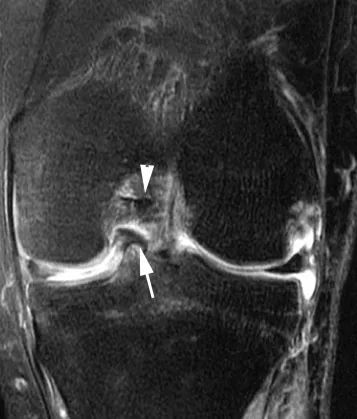

Были подтверждены и другие признаки МРТ, такие как отсутствие галстука-бабочки, знак перевернутого мениска или фрагменты мениска, смещенные непосредственно в межмыщелковую область на миллиметровых фронтальных изображениях (рис. 9) или аксиальных изображениях.

Рис. 9 Смещенная рукоятка ковша в прорези.Фронтальное PD-взвешенное изображение после подавления жира.Смещенный фрагмент мениска (стрелка) контактирует с ПКС (стрелка).